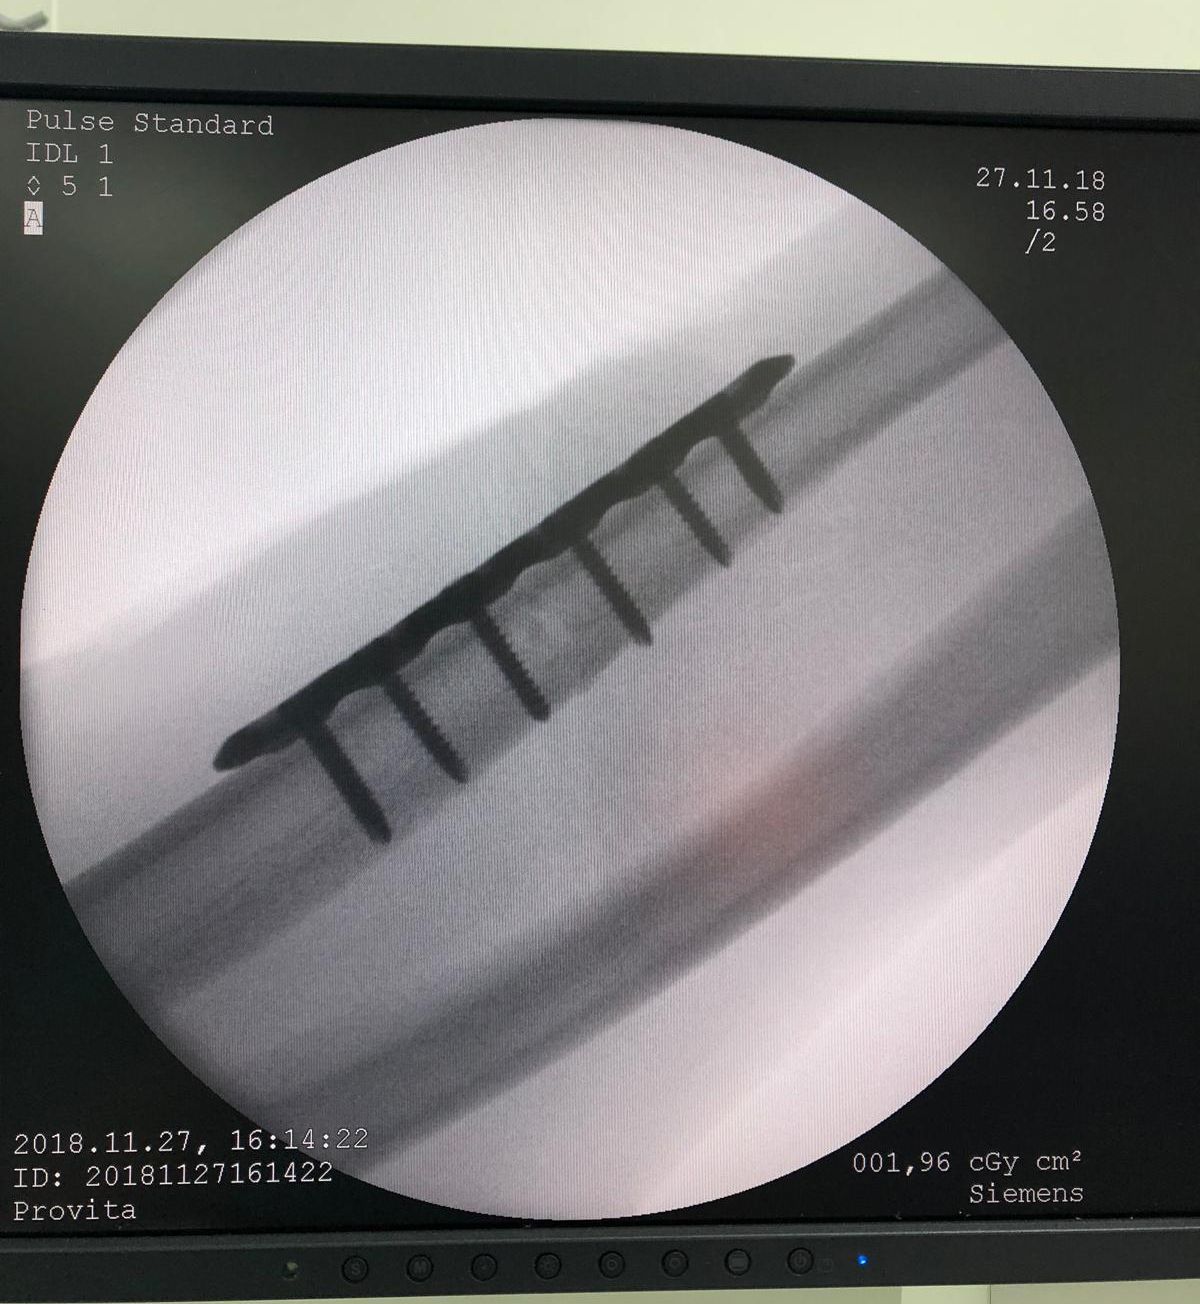

*Așa arată tija de titan care i-a fost montată lui Straton în mâna dreaptă!

Lui Cătălin i-a fost fixată o tijă de titan cu șase șuruburi. Tija trebuie scoasă în doi ani, dar e nevoie de o nouă operație, ceea ce-l sperie pe Straton.